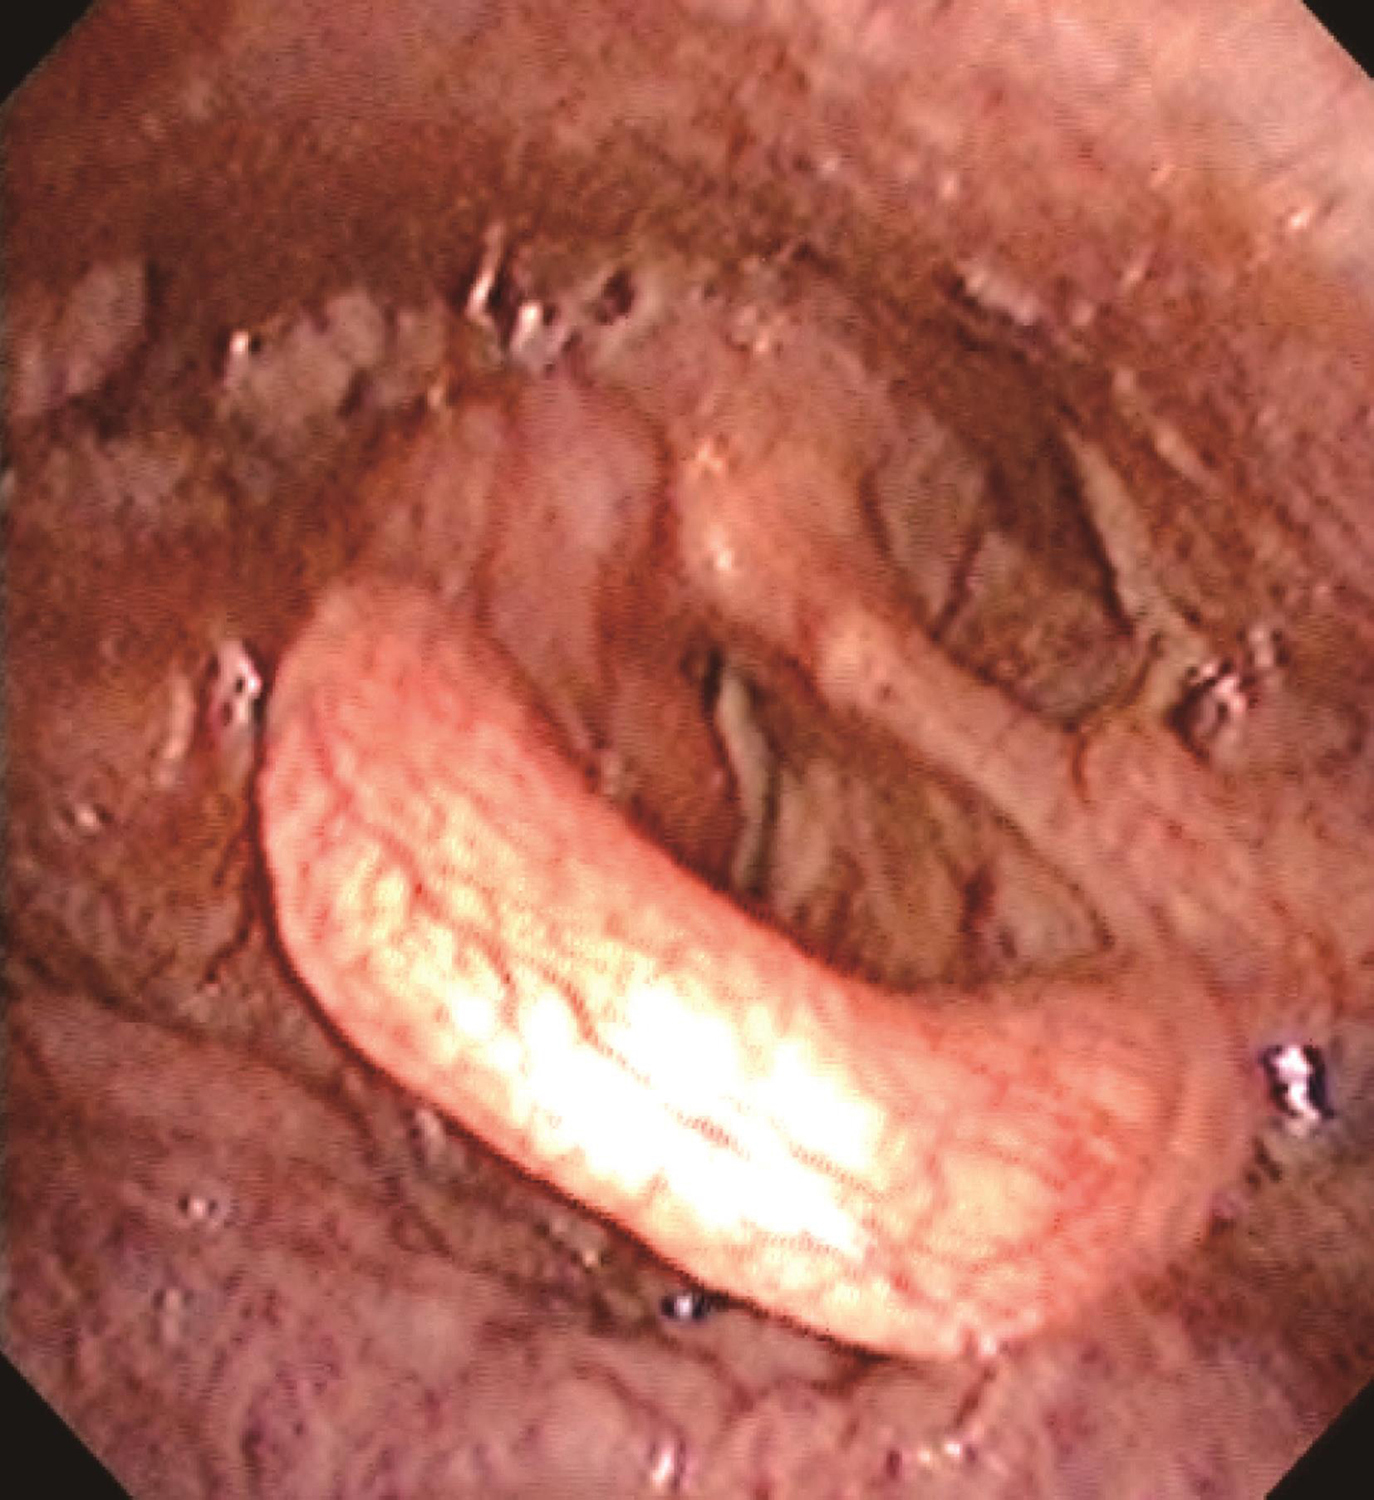

1.2014年1月10日电子喉镜检查

鼻咽部黏膜光滑,未见明显异常。口咽双侧扁桃体无肿大。舌根部淋巴滤泡略增生。右侧梨状窝内侧壁灰白粗糙新生物,形态不规则,累及右侧梨状窝外侧壁、会厌右侧缘和右侧杓会厌皱襞,右侧披裂黏膜及右侧室带肿胀,右侧声带固定,左侧声带活动正常,杓间区及环后区黏膜光滑(图1~图3)。

图1右侧梨状窝内侧壁灰白粗糙新生物